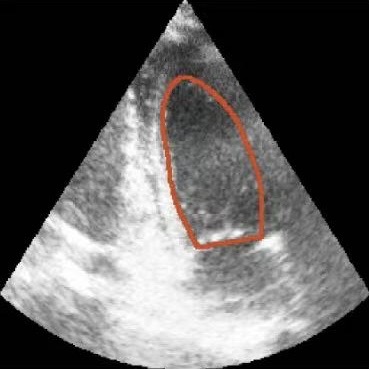

Challenges in Echocardiography Segmentation 超声心动图视频分割面临的挑战

Echocardiography segmentation faces several challenges such as low contrast, speckle noise, and signal dropout. 超声心动图视频分割面临着诸如低对比度、斑点噪声和信号丢失等多重挑战。

Noise

(a)

Blur

(b)

Shape

(c)

Scale

(d)

Cycle

(e)

Dropout

(f)

Figure 2. Illustrative challenges for echocardiography video segmentation: (a) speckle noise, (b) indistinct or blurred contours, and (c-f) the substantial changes in the target’s shape and scale throughout the cardiac cycle. 图 2. 超声心动图视频分割面临的典型挑战:(a) 斑点噪声,(b) 轮廓不清或模糊,以及 (c-f) 在整个心动周期中目标的形状和尺度发生的显著变化。